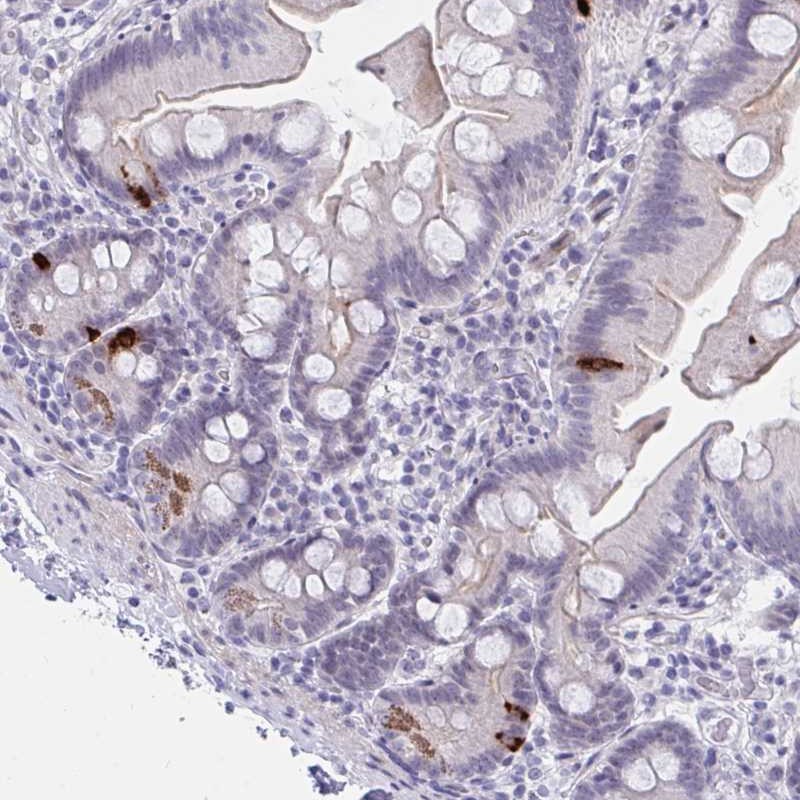

Immunohistochemical staining of human small intestine shows strong cytoplasmic positivity in endocrine cells. Paneth cells were moderately stained.